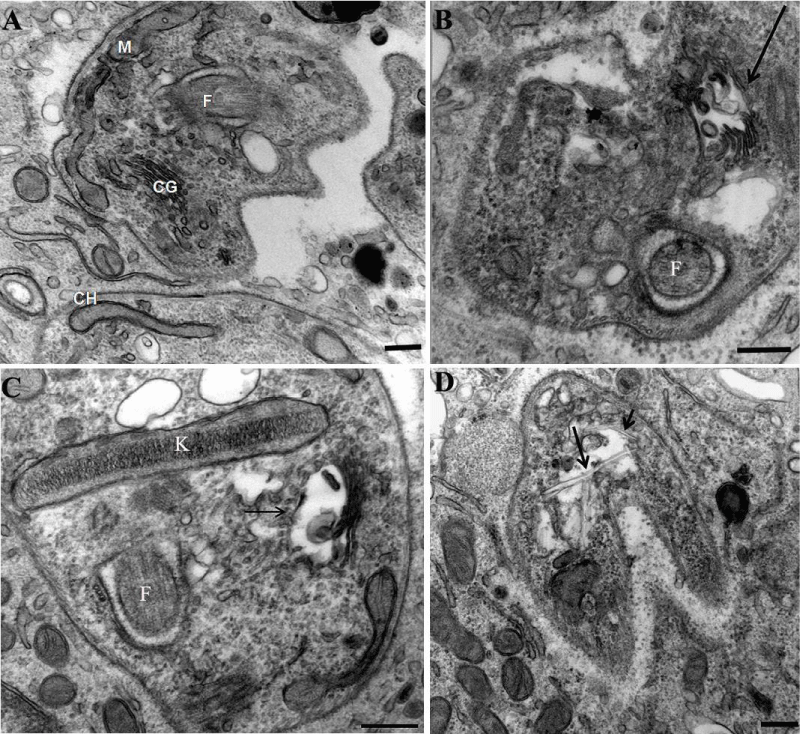

In a previous manuscript, we described the fine structure of control and drug-treated epimastigote and amastigote forms of T. cruzii [28]. T. dionisii epimastigotes treated with 1µM posaconazole or with 5 µM amiodarone for 72 hours were analyzed by scanning electron microscopy (SEM) and transmission electron microscopy (TEM). SEM analysis of untreated T. dionisii epimastigotes revealed an elongated shape with a smooth cell surface (Figure 3A). After treatment with posaconazole, the flagellum becames shortened (Figure 3B - arrows). Treatment with amiodarone promoted an epimastigotes changed from their typical elongated shape to a spherical shape (Figure 3C - arrow), where the presence of more than one flagellum in the same twisted and rounded cell body can be observed (Figure 3C - arrowhead). By TEM, after treatment with 1µM posaconazole, there was a drastic alteration in the Golgi complex, i.e., disorganization of the cisternae leading to the appearance of dilated and empty spaces (Figure 4B), morphology not observed in untreated epimastigotes (Figure 4A - GC). The formation of vesicles in the plasma membrane of the parasite (Figure 4C - arrow)as well as the presence of endoplasmic reticulum involving intracellular structures suggesting an autophagic process (Figure 4C - bold arrow) after treatment with 5µM amiodarone. The subpelicular microtubules did not present any type of abnormality after treatment (Figure 4C - arrowhead). Ultrastructural analysis of intracellular amastigotes treated with 0,25nM posaconazole (Figure 5B) and 3µM amiodarone (Figure 5C) by TEM demonstrated alterations in the Golgi complex including mischaracterization of its lamellae (Figure 5B-C arrows) when compared with untreated amastigotes. When intracelullar amastigotes were treated with posaconazole also demostrated a presence of internal membranes, suggesting the begin of authophagic process (Figure 5D).

Figure 5: Transmission electron micrographs of intracellular amastigotes after 24 hours of treatment with posaconazole and amiodarone. (A) Untreated amastigotes inside peritoneal macrophages display a normal morphology. N, nucleus; k, kinetoplast; F, flagellum; G, Golgi). (B) After 24 hours of treatment with 1 nM posaconazole, amastigotes appear with autophagic structures (arrow) and dilated Golgi complex lamellae (asterisks). (C–D) Treatment of intracellular amastigotes with 0.5 µM amiodarone caused alterations in the kinetoplast (k), with membrane detachment (arrow) and appearance of internal vesicles (arrowhead).

The electron microscopy data also showed that the effects of the three compounds on T. dionisii structural organization were the same as described previously for T. cruzii [28]. These include the following features: (a) swelling in the mitochondrion–kinetoplast complex, (b) alteration of the Golgi complex and (c) formation of autophagosomes characterized both by their morphological appearance on TEM and by LC3-B labeling as seen by immunofluorescence microscopy. These findings indicate parasite death due to an autophagic process as previously reported for T. cruzii [28].